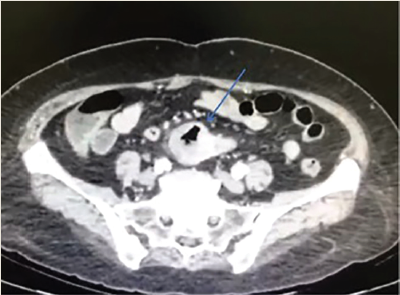

Ingresó por área de urgencias de nuestra unidad hospitalaria tras referir cuadro clínico de 48 horas de evolución caracterizado por dolor abdominal tipo cólico localizado en epigastrio y mesogastrio de gran intensidad (8/10 EVA), sin síntomas acompañantes ni exacerbantes. Al examen físico dirigido, la paciente presentaba signos vitales dentro de parámetros normales, abdomen leventemente distendido, con disminución de ruidos hidroaéreos, doloroso a la palpación superficial y profunda en epigastrio, rebote negativo. Se toman exámenes de laboratorio con presencia de leucocitosis (13,800), proteína C reactiva (PCR) elevada (7.59) y resto de laboratorios dentro de parámetros normales. Debido a la respuesta inflamatoria y persistencia de dolor abdominal, se realizó tomografía abdominal con contraste intravenoso en donde se reportó imagen sacular de 34 × 36 mm, localizado en línea media con gas en su interior dependiente de íleon distal, con pared de 18 mm y reforzamiento en fase arterial y venosa, además de discreta estriación de grasa mesentérica; todos hallazgos en relación con un probable divertículo de Meckel complicado (figura 1).

Figura 1 Tomografía abdominal con contraste intravenoso que muestra una imagen sacular en línea media con gas en su interior en íleon distal, pared 18 mm con reforzamiento en fase arterial y venosa